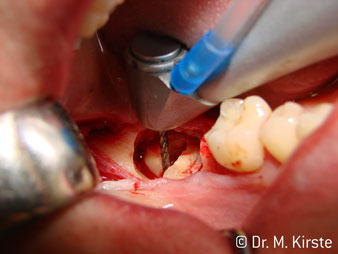

Угол 45° наконечника был выбран специально с учетом широкого круга преимуществ. Коллеги, которые работают в хирургии, и для которых этот наконечник был изначально создан, быстро оценят возможность эффективно работать в очень стесненном пространстве. В частности, при удалении зуба мудрости (рис. 2) не нужно сильно раздвигать мягкие ткани в области щеки (рис. 3). Конструкция головки наконечника в сочетании с небольшим поворотом головки во время препарирования позволяет быстро и безопасно выполнять работу в области задних коренных зубов.

Профессиональная конструкция подшипников внутри головки обеспечивает тихую работу бора; впечатляет атравматичное разделение зуба и корня (рис. 4-9).

Fig. 1

Fig. 3